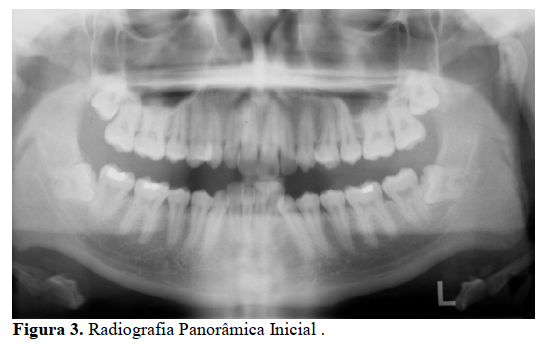

O paciente R.R.M., 21 anos, procurou a clínica ortodôntica com a queixa de apinhamento anteroinferior. Na análise facial, constatou-se que o paciente apresentava perfil convexo, selamento labial passivo e suave aumento do terço inferior da face (Figura 1 A-C).

No exame clínico intrabucal o paciente apresentava oclusão de Classe I com desvio da linha média superior de 1 mm para a direita, e um trespasse vertical anterior de 5mm com apinhamento anteroinferior, os dentes apresentavam-se íntegros quanto ao tamanho, forma e estrutura(Figura2 A-E).